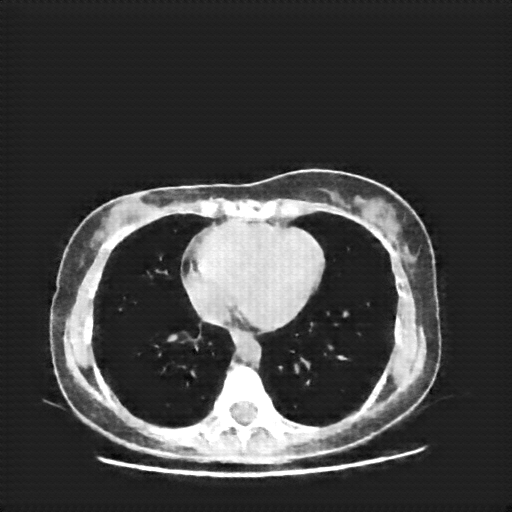

Original NATIVE CT scan (input)

Full window (WL 1023.5, WW 4095 β†’ Low βˆ’1024, High +3071)

Actual HU range: [-160.0, 240.0]